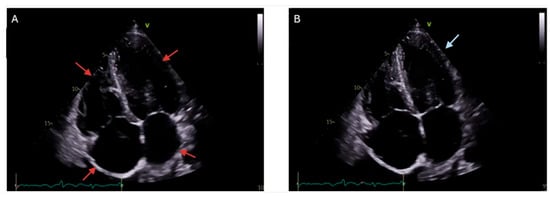

| Echocardiography [81] | Increased wall thickness, diastolic dysfunction | Widely available, non-invasive, first-line imaging, real-time assessment of cardiac function | Limited sensitivity for early iron deposition, operator-dependent, poor tissue characterization |